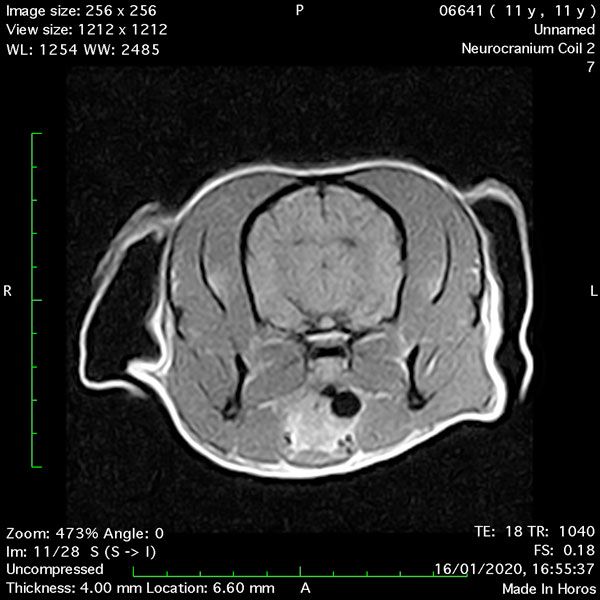

- Transverse T1 – Spin Echo T1 (post-contrast) (Figure 4);

MRI images were viewed in DICOM format (Digital Imaging and Communications in Medicine) (Figures 1-7) and assessed in-house under the guidance of a board-certified radiologist. The series were evaluated for changes in intensity in the T1- and T2-weighted sequences (T1w and T2w, respectively). There was a 4mm x 7mm x 7mm intra-axial, wedge-shaped hyperintense reasonably-well demarcated region in the right cerebrum visible in the T2w images (Figures 2-3). This was consistent with a focal infarct. No contrast enhancement, anatomical abnormality nor space occupying lesion was noted in the T1w sequences (Figure 1, Figure 4). There was no observed pathology on assessment of the FLAIR images (Figure 5).

Figures 1-7: Images obtained with MRI depicted in sequential order and assessed under the guidance of a board-certified radiologist in-house.